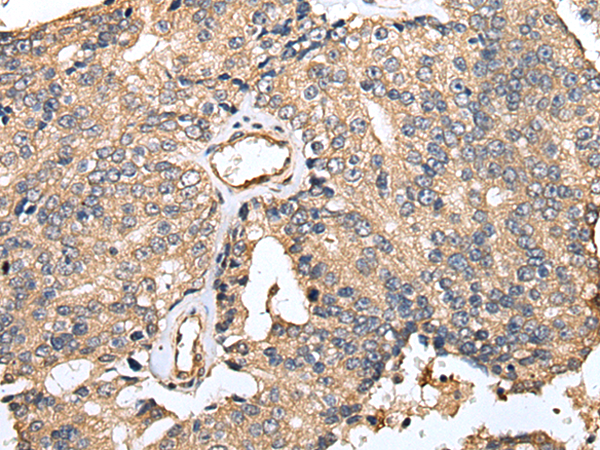

IHC positive control:

Human prostate cancer and Human tonsil

IHC Recommend dilution:

25-100